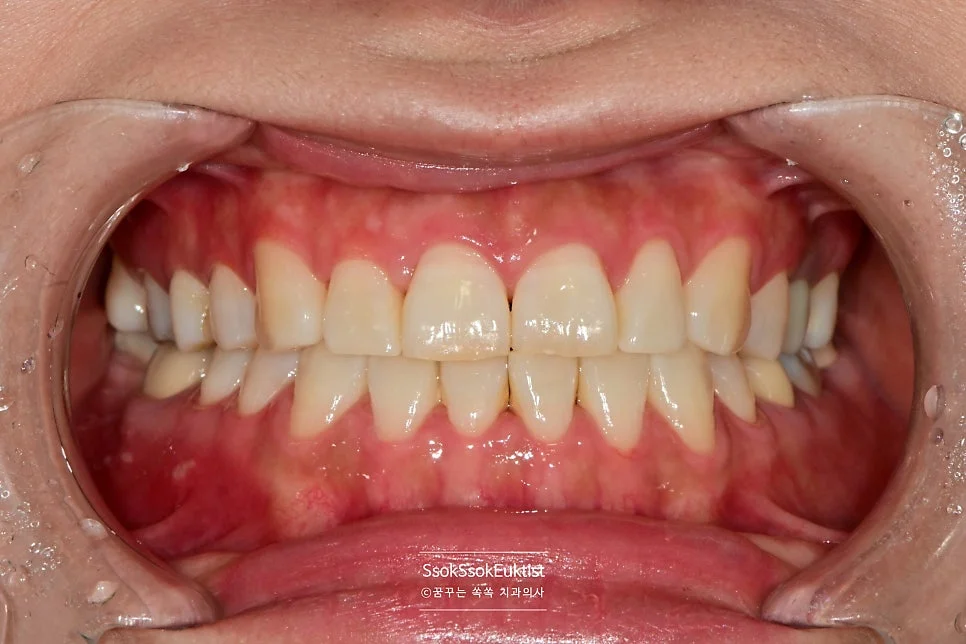

치료 전 구강 정면 — 겉으로는 큰 이상이 보이지 않지만 치아 사이에 충치가 숨어 있습니다